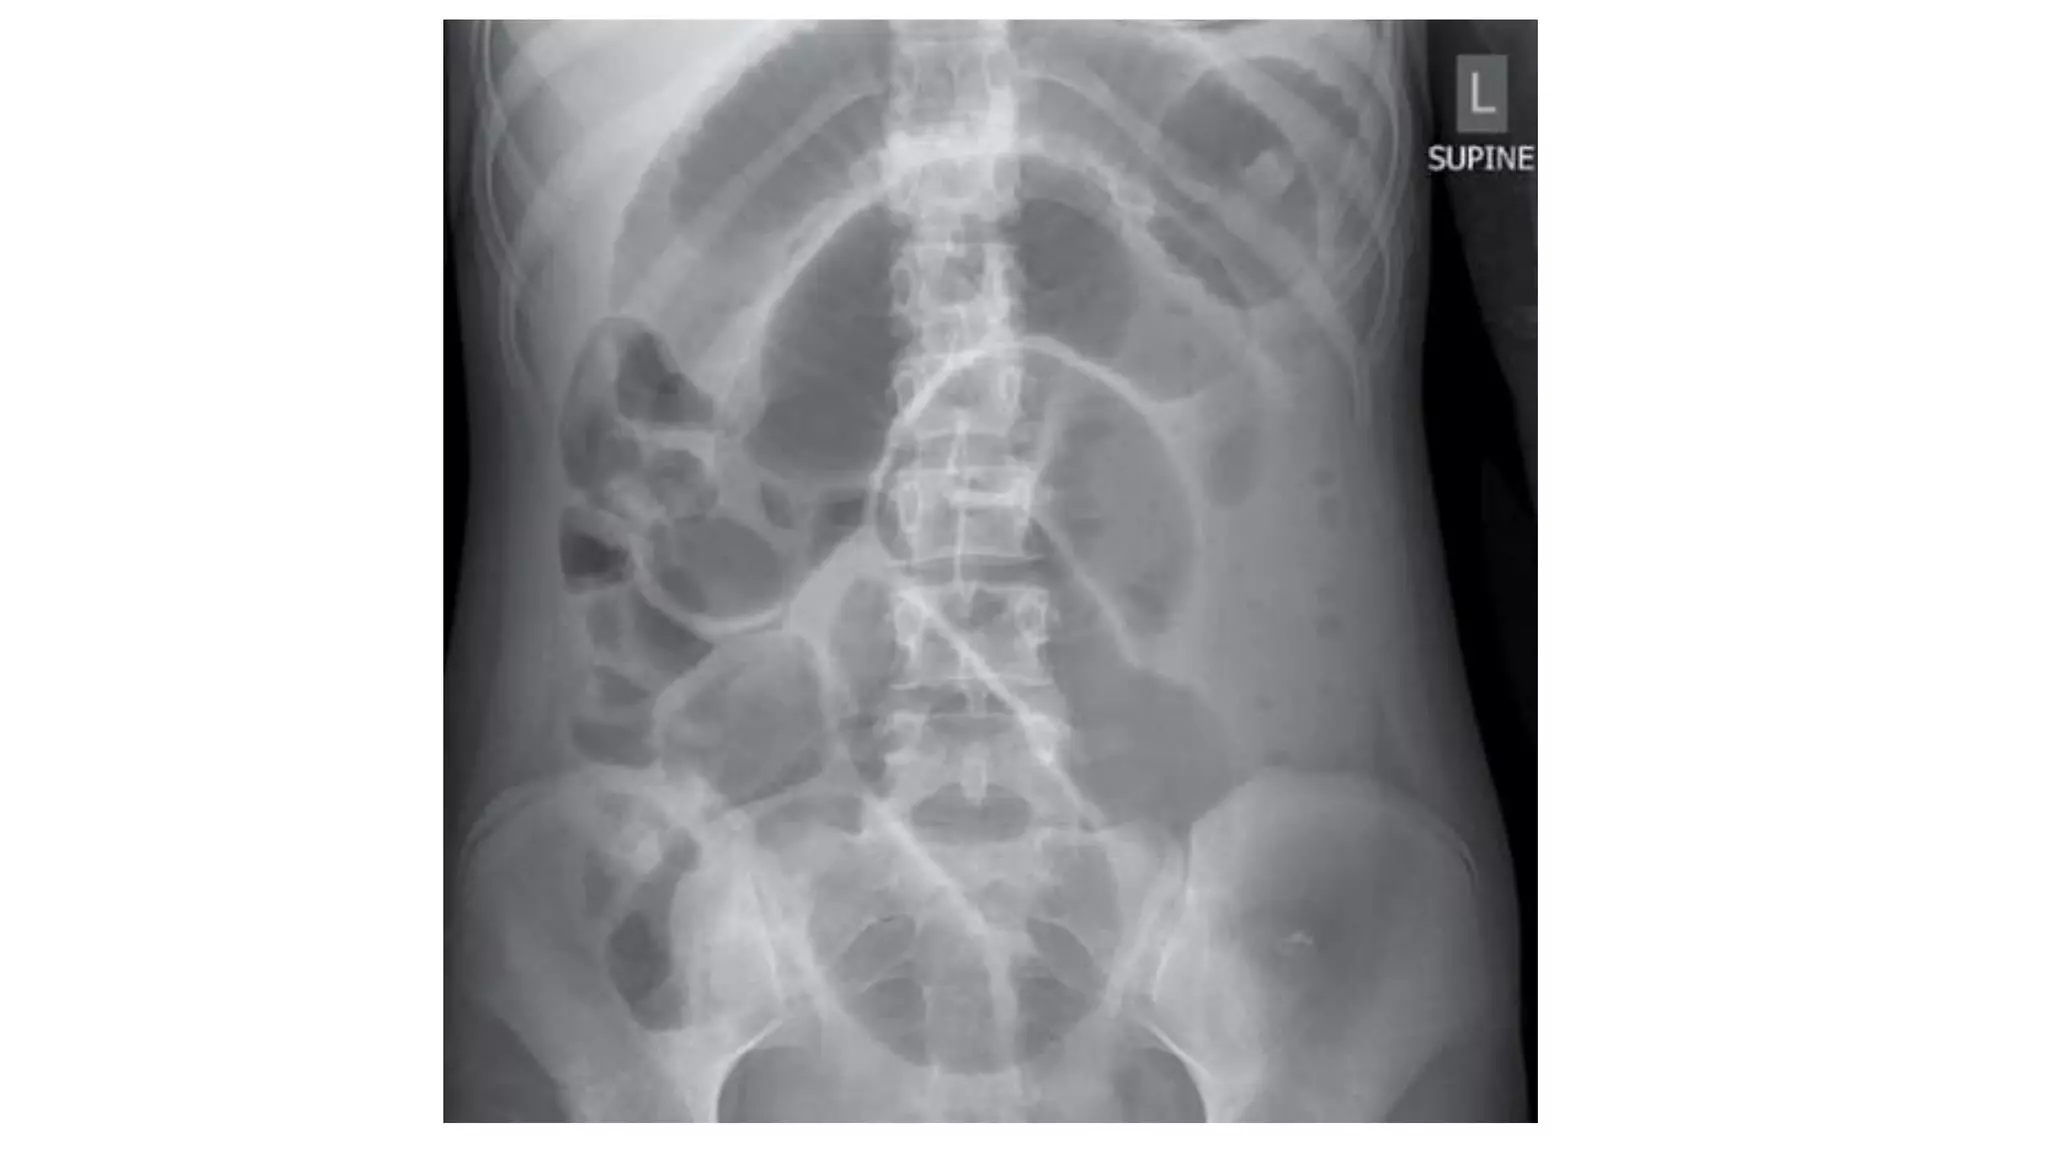

Radiological features in large bowel obstruction

• Colonic distension usually visualized in the periphery

• show the hustrations of the Taenia Coli.

• absence of rectal air and air fluid level if ileocecal valve incompetent

• May also demonstrate the cause of obstruction (volvulus)

• Dilation >3 cm: The small bowel is dilated if it measures over 3 cm in

diameter.

• Central location: The dilated loops are more likely to be centrally

located on the abdominal radiograph.

• Valvulae conniventes: These are the mucosal folds of the small

intestine. They are thin, closely spaced and classically seen as a

continuous thin line across the entire width of the bowel.

• Air fluid level in upright position